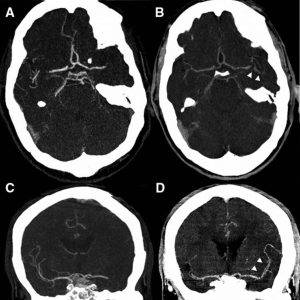

⚫ سی تی آنژیو گرافی: در این روش ماده حاجب از طریق ورید بیمار وارد جریان خون شده و دستگاه می تواند به وسیله یک نرم افزار رایانه اي، تصاویر سه بعدی دیجیتال را از عروق کرونری ثبت کند.

⚫ آنژیو گرافی: در این روش ماده حاجب به مسیر شریانی دست ها یا پاها تزریق می شود و تصاویر عروق به صورت فیلمبرداری دیجیتال و از زوایای مختلف به دست میآید.

بر کسی پوشیده نیست که دقت سی تی آنژیوگرافی به پیشرفته بودن دستگاه وابسته است. عروق کرونری در هر تپش قلب، دچار انقباض و انبساط می شوند و مدام در حرکت هستند؛ بنابراین دستگاه سی تی آنژیوگرافی باید بسیار دقیق و حساس باشد تا بتواند حرکات ریتمیک قلب را به درستی باز تولید کند و تصاویر سه بعدی عروق قلبی که فقط حدد ۲ تا ۳ میلی متر قطر دارند، مخدوش نشوند.

سی تی آنژیو گرافی در واقع نوعی سی تی اسکن است با این تفاوت که در سایر سی تی اسکن ها فرد باید بی حرکت بایستد یا بخوابد تا دستگاه تصویر محل مورد نظر را اسکن کند اما دستگاه سی تی آنژیوگرافی قادر است از رگ در حال حرکت تصویر کامپیوتری ثبت کند؛ تصویری مجازی که به دلیل حرکت ماهیچه ها و در نتیجه عروق قلب(تپش قلب) به ناچار خیلی دقیق نخواهد بود.

اما آنژیوگرافی عروق کرونری به مراتب دقیق تر از دستگاه های سی تی آنژیوگرافی عمل می کند. در آنژیو گرافی عروق کرونری ماده حاجب به رگ تزریق شده و از رگ فیلمبرداری می شود؛ به همین دلیل تکان های رگ مانعی برای ثبت دقیق تصاویر نخواهند بود.

اگرچه در تشخیص اولیه بیماری عروق کرونری میزان دقت سی تی آنژیو گرافی و آنژیوگرافی عروق کرونری تقریبا به یک میزان قابل قبول است اما زمانی که نیاز به تشخیص دقیق محل تنگی عروق، طول تنگی و درصد آسیب عروق باشد، سی تی آنژیوگرافی هرگز دقت آنژیوگرافی عروق کرونری را ندارد و دقت این دو با هم قابل مقایسه نیست و فقط آنژیو گرافی عروق کرونری قادر به تشخیص این نکات ظریف است.